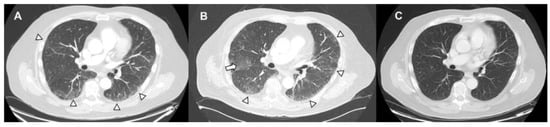

Pulmonary Complications of Cancer Therapy: Clinical Presentations, Imaging Patterns, and Management Strategies

by Bilal Zafar, Tasmea Haque, Miranda Tan, Ritika Singh, Lara Bashoura, Ajay Sheshadri, Maria Azhar and Saadia A. Faiz

Background and objectives: Therapeutic agents for cancer can cause unique pulmonary toxicities and mimic other conditions. The advent of new targeted molecular and immune therapies has changed the landscape of cancer treatment. These adverse events pose diagnostic and therapeutic challenges. This review aims to summarize the clinical presentations, radiographic patterns, and management strategies for noninfectious pulmonary complications associated with cancer therapies. Materials and methods: A literature review was conducted focusing on drug-induced lung injury (DILI), radiation-induced lung injury (RILI), pleural disease, pulmonary vascular complications, and other inflammatory conditions in patients with cancer. The data sources included clinical trials, guideline recommendations, observational studies, and expert consensus addressing incidence, pathophysiology, imaging findings, and treatment approaches. Results: Noninfectious pulmonary sequelae of anti-neoplastic therapies encompass a broad spectrum of etiologies. DILI occurs in up to 30% with variable onset and severity. The patterns can be diverse but include interstitial pneumonitis, organizing pneumonia, and diffuse alveolar damage. RILI is common and influenced by the radiation dose, volume, and concurrent therapies, and it may have both acute and chronic clinical and radiographic presentations. Pleural disease may arise from radiation and other agents, and the determination of etiology can impact management. Pulmonary vascular disease arises from many different etiologies, including therapies such as tyrosine kinase inhibitors and proteosome inhibitors, thromboembolic disease, as well as rare processes, including pulmonary veno-occlusive disease. Other conditions such as transfusion-related lung injury, cryptogenic organizing pneumonia, and interstitial lung abnormalities can also further complicate the diagnosis. Conclusions: Noninfectious pulmonary complications related to cancer therapies are diverse and often indistinguishable from infectious or malignant processes. The integration of clinical history, imaging, and selective invasive testing are needed for a timely diagnosis. Management typically involves withdrawal of the offending agent and corticosteroids, with immunosuppressive therapy reserved for severe or refractory cases. The awareness of these entities and early recognition are critical to optimizing outcomes. Full article

(This article belongs to the Section Pulmonology)